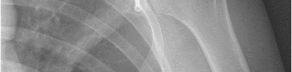

Question 10:

A 25-year-old female sustains a Pauwels type III femoral neck fracture after a motor vehicle accident. Which biomechanical force makes this specific fracture pattern particularly prone to fixation failure and varus collapse?

Correct Answer: Shear forces

Explanation:

The Pauwels classification of femoral neck fractures is based on the angle of the fracture line relative to the horizontal. A Pauwels type III fracture is highly vertical (angle >50 degrees). Because of this vertical orientation, normal joint reactive forces across the hip are converted primarily into high shear forces across the fracture line, predisposing the fracture to varus collapse, loss of fixation, and nonunion compared to the more compressive forces seen in horizontal fractures.